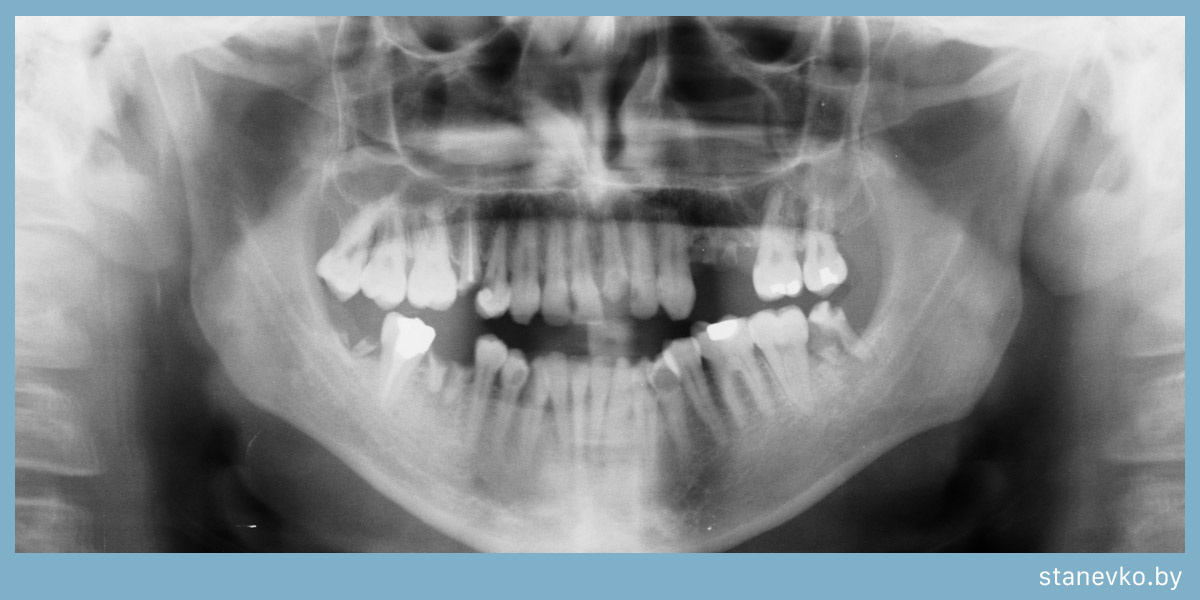

Удаление зубов: Что нужно знать перед процедурой?

Еще один вариант, это неправильное расположение зуба в челюсти. Он может травмировать десну, увеличивая шанс возникновения онкологических заболеваний. Беречь такие зубы не нужно, врач лишь определит, где правильнее будет провести удаление – в поликлинике или в стационаре.